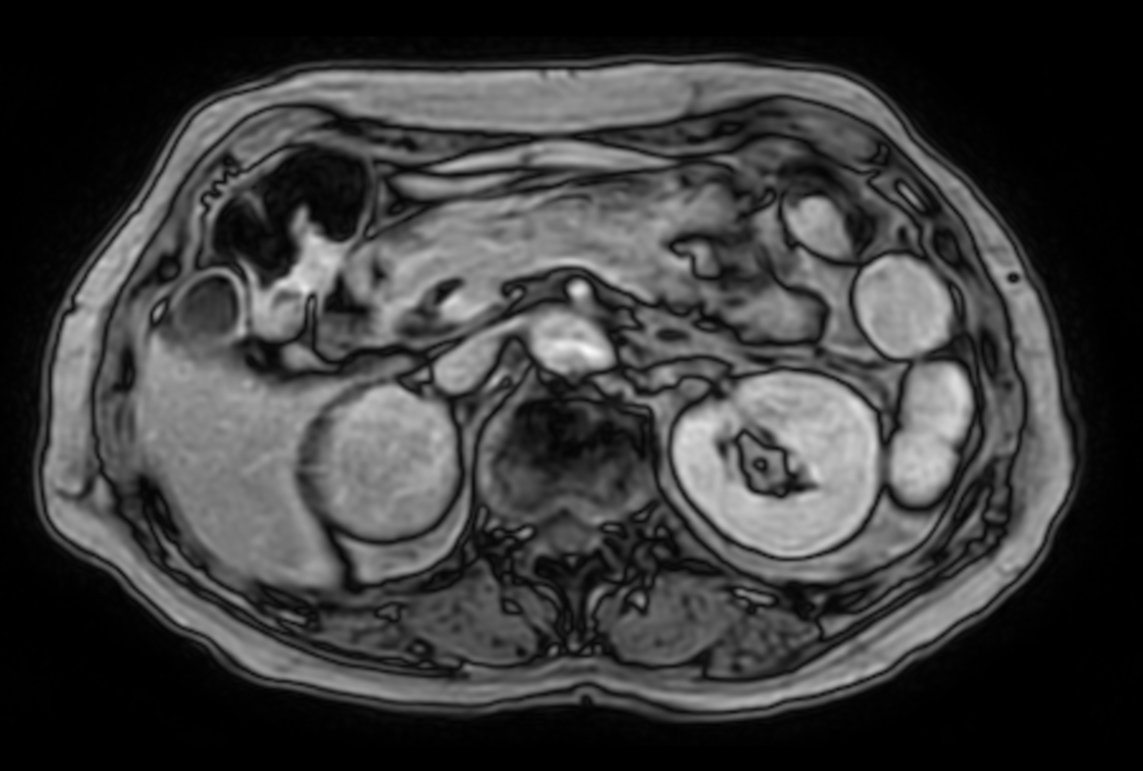

Patient with a kidney lesion. The ExamCard includes techniques for 3D imaging (PelvisVIEW, eTHRIVE) allowing for multiple image directions in one single scan, efficient fat-free imaging over large field-of-views (mDIXON XD), a multi-phase contrast-enhanced sequence (4D FreeBreathing) to improve imaging confidence and Compressed SENSE to accelerate the entire exam.

DWI b800 (ADC)